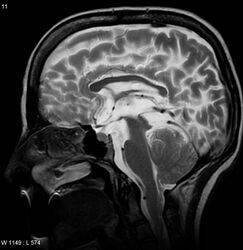

A sagittal FLAIR MRI scan, from a patient with an Arnold-Chiari malformation, demonstrating tonsillar herniation of 7 mm.

Diagnosis is made through a combination of patient history, neurological examination, and medical imaging.[14] Magnetic resonance imaging (MRI) is considered the preferred imaging modality for Chiari malformation.[15] The MRI visualizes neural tissue such as the cerebellar tonsils and spinal cord as well as bone and other soft tissues. CT and CT myelography are other options and were used prior to the advent of MRI, unfortunately the resolution of CT based modalities do not characterize syringomyelia and other neural abnormalities as well.[citation needed]

By convention, the cerebellar tonsil position is measured relative to the basion-opisthion line, using sagittal T1 MRI images or sagittal CT images.[16] The selected cutoff distance for abnormal tonsil position is somewhat arbitrary, as not every person will be symptomatic at a certain amount of tonsil displacement, and the probability of symptoms and syrinx increases with greater displacement; however, greater than 5 mm is the most frequently cited cutoff number, though some consider 3–5 mm to be "borderline,"; pathological signs and syrinx may occur beyond that distance.[16][17][18] One study showed little difference in cerebellar tonsil position between standard recumbent MRI and upright MRI for patients without a history of whiplash injury.[13] Neuroradiological investigation is used to first rule out any intracranial condition that could be responsible for tonsillar herniation. Neuroradiological diagnostics evaluate the severity of crowding of the neural structures within the posterior cranial fossa and their pressure against the foramen magnum. Chiari 1.5 is a term used when both brainstem and tonsillar herniation through the foramen magnum are present.[19]